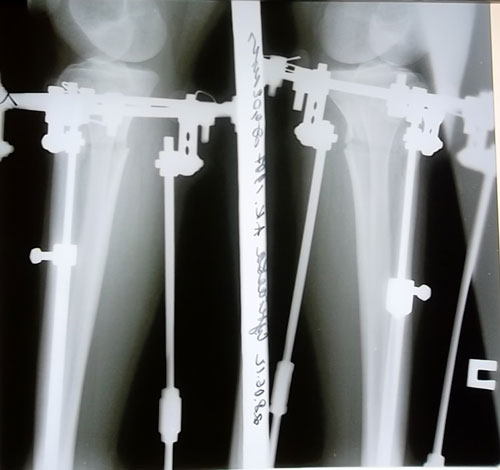

рентгеновские снимки на 11- ый день после операции. Кости выровнены, вышла на фиксацию!

Дата операции 18.06.2012г.

Аппараты сняты 22.08.2012г.

Аппаратная жизнь 64 дня.